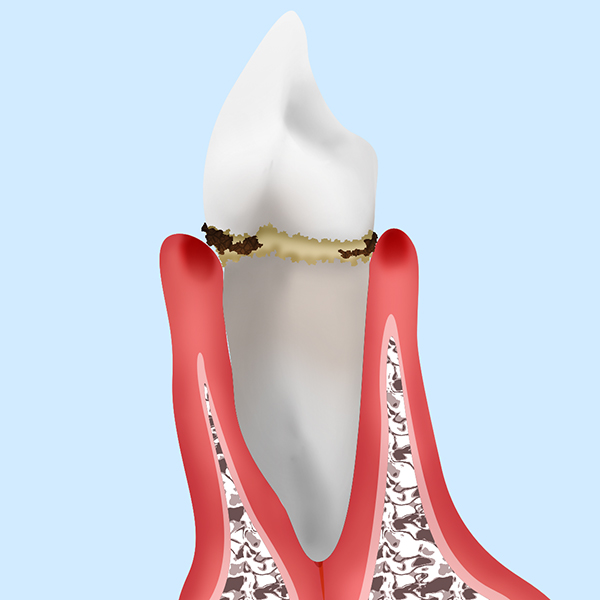

この歯垢(プラーク)が長い間、歯の表面に付着していると石灰化して歯石になります。歯石になると硬くこびり付き歯ブラシでは取れない汚れとなります。

歯垢も歯石も歯周病の原因になります。

歯周病菌の存在する部位は主に歯茎を境にして2部位に分けられます。

歯茎より上の部分(歯肉縁上)と歯茎より下の部分(歯肉縁下)です。歯肉縁上は目に見える部分に付着しているため痛くなく、綺麗に取ることが簡単にできます。

ただ見える所だけを綺麗にしても、歯茎の中に歯周病菌が付着していれば意味がありません。

見せかけだけの綺麗な状態

これでは意味がありません。